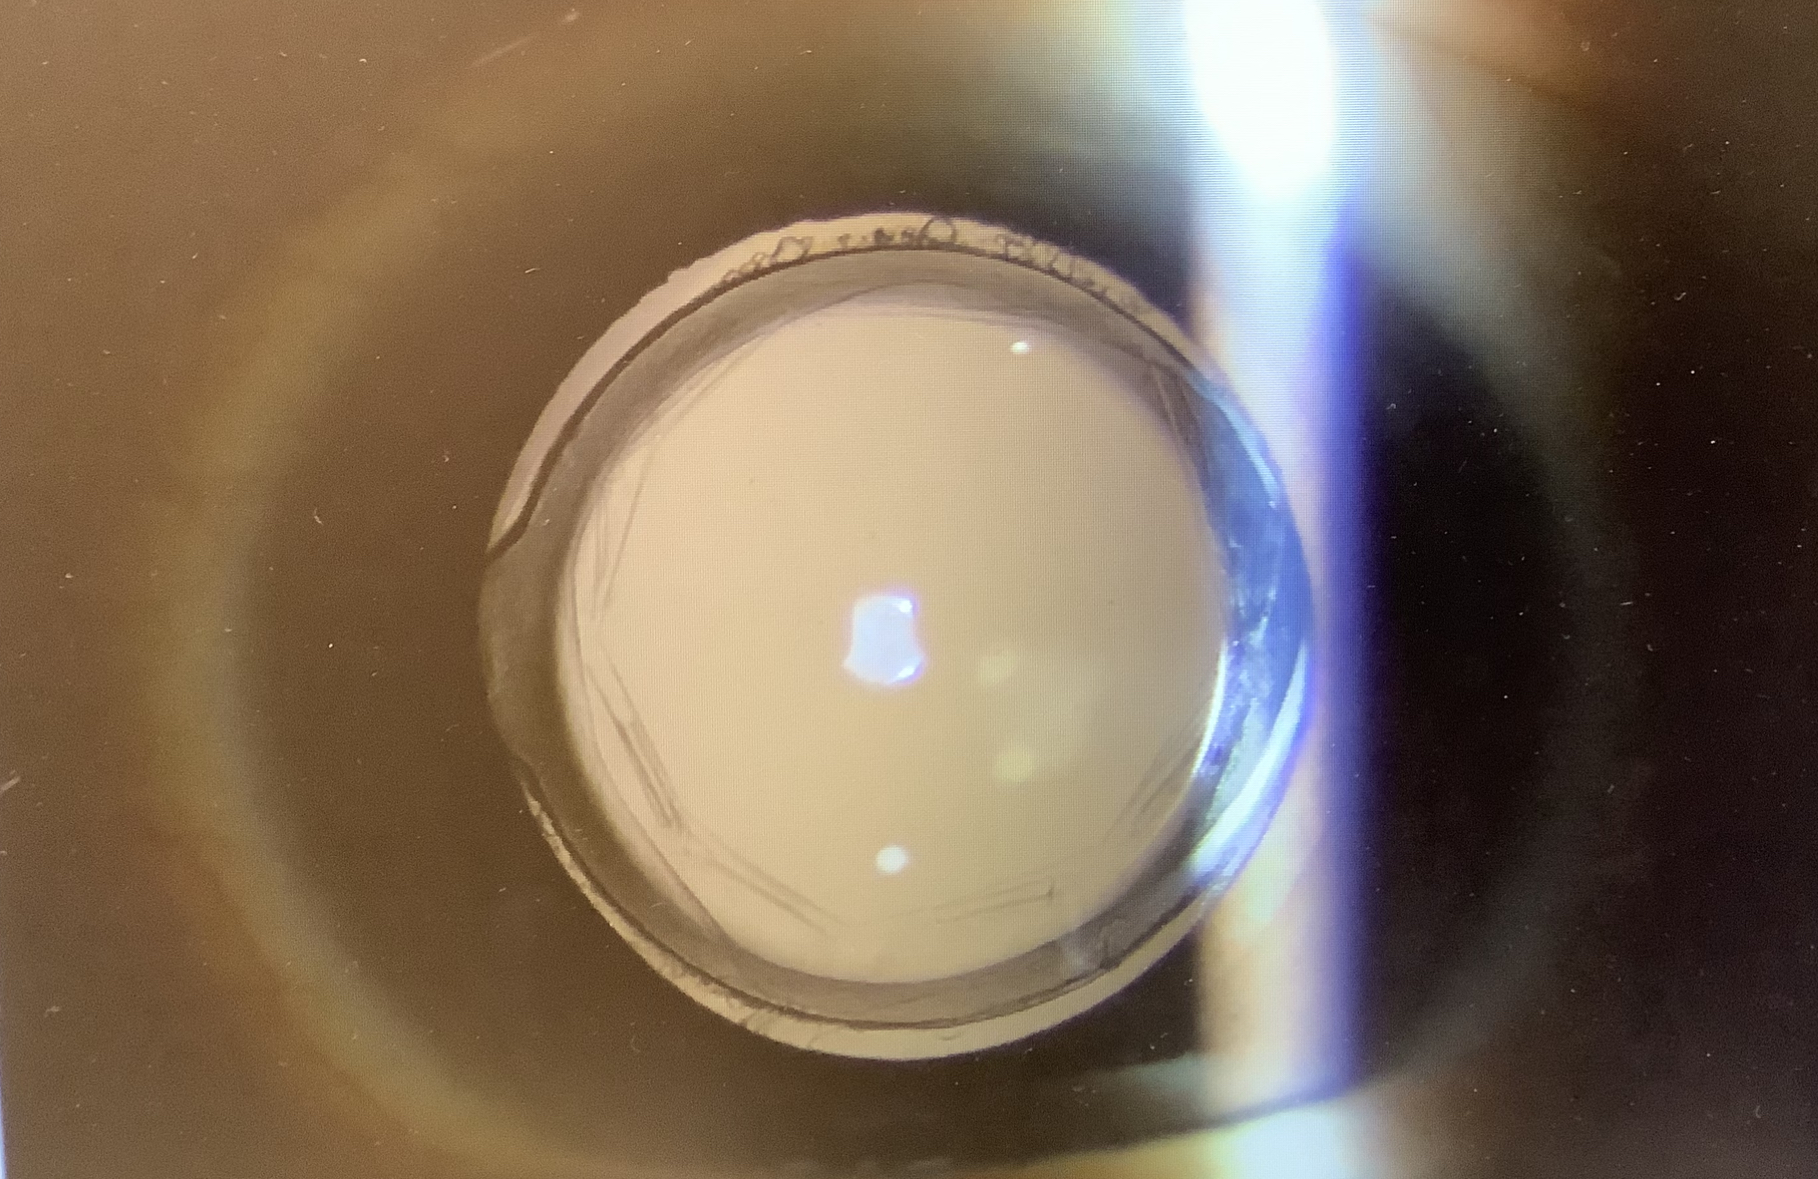

白内障手術の後のピントを変える場合、眼内レンズを入れ換えれば一番、単純で根本的な対応になると考えていますが、この患者さまの場合、見えにくさの原因が後発白内障では?とされ、既にYAGレーザーで後嚢が切開されており、レンズの入れ換えがやりにくい状況になっていました。入れ換えはできなくはないと思われますが、眼には負担になってしまい、よくなるかどうか不確定な要素が強い状況では、選択しにくい治療と思いました。一方、アドオンレンズは後嚢の有無は難易度に全く影響せず、今入っている眼内レンズの上に乗せてあげればよいだけの比較的侵襲の少ない治療で、尚且つ、もし入れてうまくいかなかった時でも取り出しは容易で“後戻りができる”治療でもあり、治療効果の見通しがはっきりしない時にはしやすい治療でもあると思います(そういう点では、後発白内障のレーザー治療をしていなくとも、アドオンレンズが第一選択になったかもしれません)。